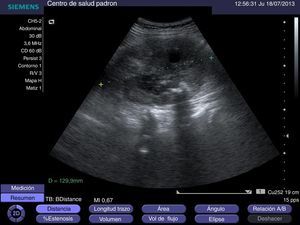

Mujer de 61 años de edad sin antecedentes de interés, que consulta en atención primaria por hematuria objetivable de 15 días de evolución. Presenta cuadro catarral en los días anteriores, sin otros datos de interés. En la exploración física se aprecia masa palpable en hipocondrio derecho. Se realiza ecografía en su centro de salud obteniéndose las siguientes imágenes (figs. 1 y 2).

La unión de hematuria y masa palpable en hipocondrio derecho nos orienta hacia un proceso maligno como primera posibilidad. En la ecografía realizada en atención primaria observamos un riñón derecho con discreto aumento de tamaño (12,9cm de longitud en el riñón derecho versus 9,5cm en el riñón izquierdo, en una mujer de 155cm de estatura) y parénquima renal muy desestructurado (es difícil ver en este caso la estructura ecográfica típica renal: corteza, médula y seno renal). También destaca la presencia de abundantes imágenes hiperecoicas con sombra posterior (sugestivo de calcificaciones groseras), sin que se observen imágenes de ectasia renal. El aumento de tamaño y la desestructuración de la arquitectura renal nos hacen pensar en enfermedad neoplásica. La presencia de las numerosas calcificaciones groseras (que no sugieren enfermedad litiásica) nos lleva a proponer una hipótesis diagnóstica muy infrecuente: carcinoma renal de tipo sarcomatoide.